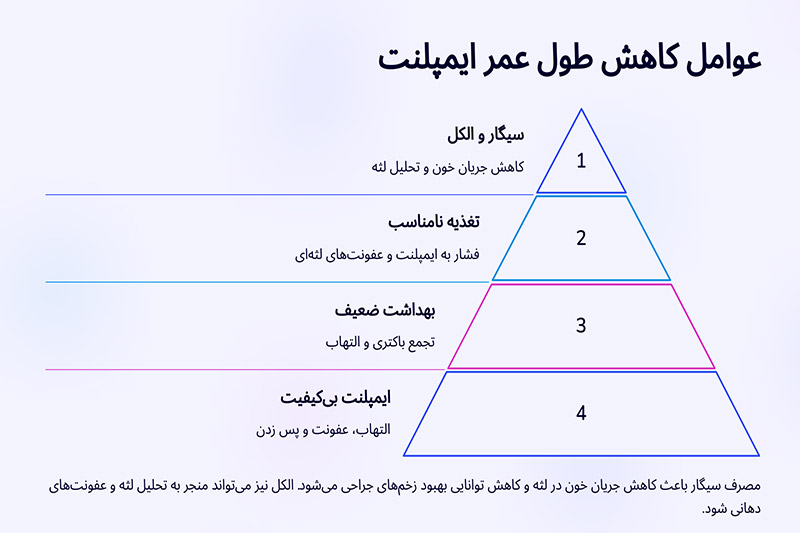

| مصرف دخانیات و الکل | سیگار کشیدن و مصرف الکل میتواند جریان خون به لثهها را کاهش داده و فرآیند بهبود را مختل کند، که این امر ممکن است به کاهش طول عمر ایمپلنت منجر شود. |

طبق تحقیقات و بررسی های به عمل آمده درخصوص طول عمر ایمپلنت های دندانی و همچنین درصد شکست آنها به این نتیجه دست یافتیم که استفاده از ایمپلنت های بی کیفیت و نامعتبر عامل اصلی بروز این قبیل مشکلات است. بدین ترتیب با انتخاب و استفاده از بهترین نوع ایمپلنت می توانید ضمن افزایش دوام و طول عمر ایمپلنت دندان، از هر گونه مشکل احتمالی جلوگیری به عمل آورید. البته باید توجه داشته باشید که ایمپلنتولوژیست ها اغلب از برندهای معتبر ایمپلنت برای کاشت دندان استفاده می کنند. برای آشنایی بیشتر با بهترین برندهای ایمپلنت دندان در سال 2023 می توانید با کارشناسان ما در وب سایت دکتر وزیری ارتباط برقرار نمایید.

5. رعایت بهداشت دهان و دندان

یکی دیگر از عوامل مهم و تأثیرگذار بر طول عمر ایمپلنت های دندانی رعایت بهداشت دهان و دندان، استفاده از بهترین دهانشویه برای ایمپلنت است. حفظ سلامت دهان و دندان ها پس از کاشت ایمپلنت از بروز هرگونه التهاب، تورم و عفونت لثه جلوگیری نموده و بدین ترتیب عمر دندان ایمپلنت شده نیز بیشتر خواهد شد. بدین منظور با استفاده روزانه از مسواک (دوبار در روز) و نخ دندان پس از خوردن مواد غذایی می توانید سلامت دهان و دندان خود را حفظ کرده و از تحلیل لثه و تحلیل استخوان فک جلوگیری کنید.

- آیا نوع تغذیه روی طول عمر ایمپلنت دندان تأثیر دارد؟

بله، مصرف غذاهای سفت و سخت میتواند به ایمپلنت دندان فشار وارد کرده و به مرور زمان باعث آسیب به آن شود. همچنین، مصرف زیاد مواد قندی و اسیدی ممکن است باعث بروز عفونتهای لثهای شده و روی ماندگاری ایمپلنت تأثیر منفی بگذارد. توصیه میشود رژیم غذایی متعادلی داشته باشید و پس از صرف غذا، بهداشت دهان و دندان را رعایت کنید.

- آیا سیگار کشیدن و مصرف الکل باعث کاهش طول عمر ایمپلنت میشود؟

بله، مصرف سیگار و الکل تأثیر منفی زیادی بر موفقیت کاشت ایمپلنت دارد. سیگار کشیدن باعث کاهش جریان خون در لثه و کاهش توانایی بهبود زخمهای جراحی میشود، در نتیجه ممکن است باعث پس زدن ایمپلنت شود. الکل نیز میتواند منجر به تحلیل لثه و عفونتهای دهانی شود که در نهایت طول عمر ایمپلنت را کاهش میدهد.